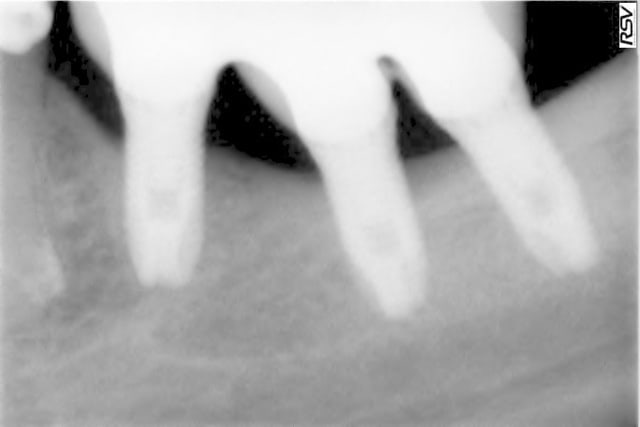

ouvre les yeux: la crétérisation est importante à 4 mois ou à un an

il y a cratérisation dans prseque tous les cas de figure: juxta ou infra-crestal.

il y a cratérisation aussi au sondage donc galère